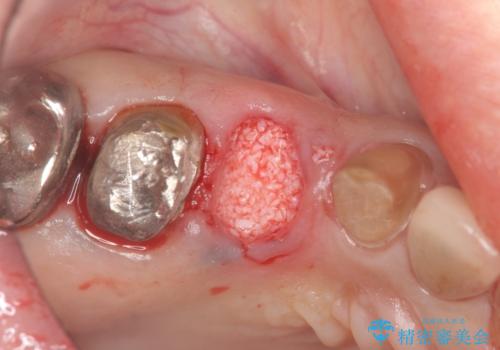

また単純に抜歯のみを行うと歯ぐきが大きく凹み、ブリッジの清掃性が損なわれることが予想されるため、抜歯時に歯槽堤保存術を行い

清掃性の高い仕上がりとなるよう配慮しています。